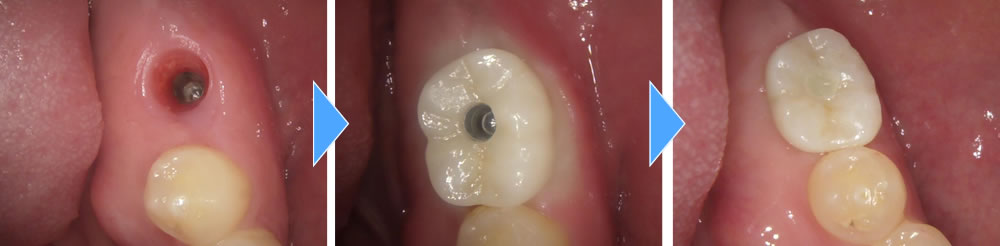

上部構造の装着・治療完了

本来であればもう一本奥にもインプラントを入れた方が奥までバランスよく噛むことができますが、金銭的に難しいとのことで患者さまと相談し、短縮歯列にて完成させました。

術後は今まで通り奥までしっかりと噛むことができ、大変満足していただいております。